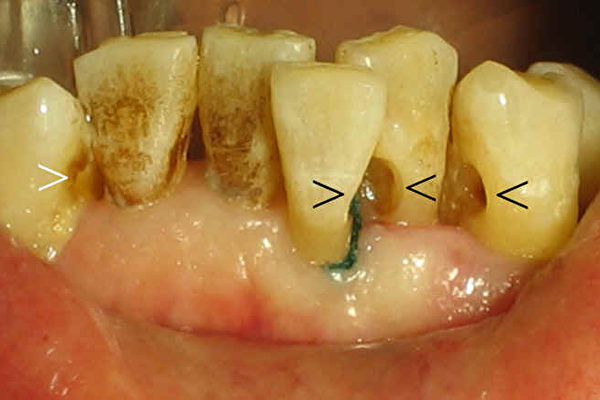

過去我們探討過牙周病與心臟病,糖尿病,嬰兒早產有關,現在科學家們發現牙周病(我們過去認為沒有甚麼了不起的疾病)也能增加我們生某些癌症的可能性。

這項研究發表於腫瘤雜誌(Lancet Oncology),研究者追蹤男性醫務工作人員近二十年,所有這些男人都有牙周病病史。研究結束時,科學家發現有牙周病的病人的癌症危險性比沒有牙周病的人高百分之十四。

我們得出這項研究結果前,已經排除吸煙等致癌因素;與牙周病有關的癌症包括肺癌,腎臟癌,胰腺癌,血液性惡性腫瘤, 如白血病。科學家老早就知道牙周病病人血液中發炎(炎症)指標很高,現在眾所周知炎症是某些癌症,心臟病,糖尿病,以及許多種疾病發病重要因素。這項研究 表明牙周病是某些癌症的促進原因,我們不得不注意啊。癌症病因不明,而且有些病因即使知道,也無法控制,例如遺傳,但是牙周病是每個人能控制的因素,好好 刷牙,天天用牙線,定期洗牙,我們為甚麼要坐以待斃,讓無聲殺手(牙周病),奪取我們的寶貴牙齒和生命呢? ◇